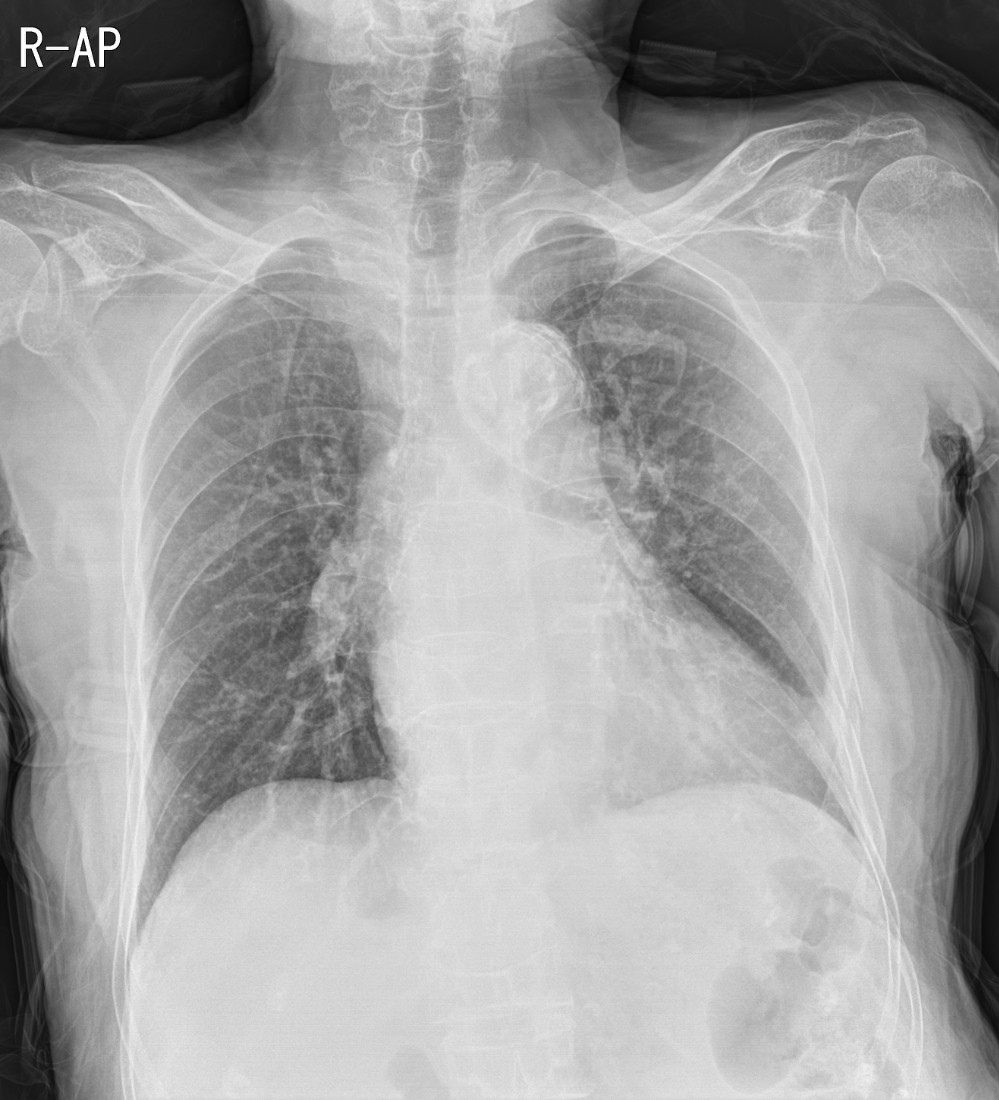

91세 여자 환자로, CT에서 왼쪽 폐에 폐암이 발견되었으나, 고령과 전신상태가 여의치 않아 수술을 포기한 분의 단순 흉부X선 영상입니다.

이전에 여러차례 촬영했던 Chest PA view는 물론 CT에서도 분명히 확인했던 왼쪽 폐의 암덩어리가 AP view에서는 확인되지 않습니다. 이렇게만 보면, 기적적으로 며칠만에 암덩어리가 사라졌든지, 과거 폐암으로 진단되었던 병변이 폐암이 아니라 국소적인 폐렴이었다 며칠만에 호전되었을 가능성도 제기할 수 있을겁니다.

폐에 병변이 의심되는 경우 가장 기초적인 영상검사는 단순흉부X선검사입니다. 특별한 제약사항이 없다면 기본적으로 서있는 자세로 Chest PA view영상을 촬영하는 것이 원칙인데, 왜 AP view가 아닌 PA view를 촬영해야 하는지를 극명하게 보여주는 사례 같아서 올려봅니다.

또한, 의대생이나 영상의학을 전공하지 않은 분이라면 위의 영상들만 보고 Chest PA view인지 AP view인지 정확하게 구별하지 못하는 분들이 있을 수 있지만, 자세히 들여다보면 AP view와 PA view를 구분할 수 있는 중요한 특징들이 잘 드러나있는 영상들입니다. 영상의학과에서 기사분들이 촬영하면서 라벨을 잘못 붙혀서 AP view영상임에도 불구하고 PA view로 잘못 기재되는 경우들이 종종 있고, 이게 나중에 문제가 되는 경우도 있기 때문에 이 둘을 구분하는 건 시험공부로든, 실제 임상영역에서든 상당히 중요한 부분이라 생각합니다.

위의 영상들을 가지고 AP view와 PA view의 구분을 할 수 있는지 잠깐 점검해보는 것도 괜찮을거라 봅니다.